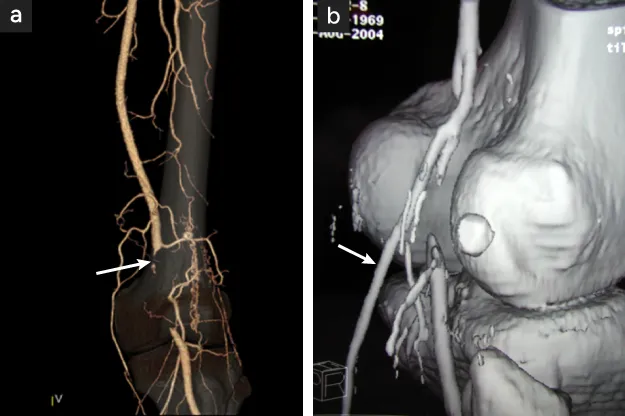

図5

図5. 膝窩動脈捕捉症候群

膝窩筋の圧迫による膝窩動脈の閉塞所見(矢印)

• 血管造影所見

• 【左膝窩動脈捕捉症候群】膝部圧迫3D造影画像